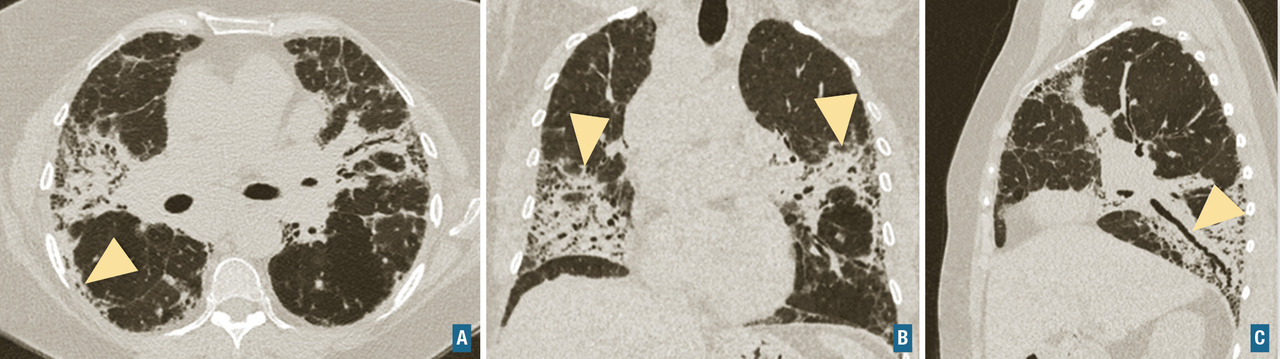

Connectivites

Des éléments évocateurs de connectivite doivent toujours être recherchés, au moins cliniquement lors du bilan d’une pneumopathie interstitielle diffuse. Les connectivites les plus fréquemment impliquées sont la poly­arthrite rhumatoïde, la sclérodermie systémique, le syndrome de Gougerot-Sjögren et les myosites auto­­immunes (dermatomyosite principalement). La présentation scanographique est le plus souvent celle d’une pneumopathie interstitielle non spécifique (fig. 7) qui peut présenter ou non des éléments de fibrose ou des condensations (pneumonie organisée). L’atteinte pulmonaire peut compliquer une connectivite connue ou au contraire être révélatrice de la maladie.

Fibrose pulmonaire idiopathique (FPI) : c’est la plus fréquente et la plus grave des pneumopathies interstitielles diffuses idiopathiques chroniques. Elle est définie par une fibrose progressive et irréversible du poumon, de cause inconnue, et survient le plus souvent chez les hommes dans leur septième décennie, fumeurs ou anciens fumeurs. La médiane de survie après le diagnostic et sans traitement est d’environ 3 ans. Les signes cliniques sont non spécifiques, et incluent une dyspnée d’effort d’apparition progressive, une toux sèche, des crépitants secs, dits « Velcro », précoces et parfois un hippocratisme digital. La fibrose pulmonaire idiopathique est caractérisée par un aspect radiologique et/ou histologique de pneumopathie interstitielle commune. L’aspect scanographique de pneumopathie interstitielle commune associe du rayon de miel, des réticulations sous-pleurales, des bronchectasies et bronchiolectasies de traction (fig. 7). Les anomalies sont de distribution basale et sous-pleurale prédominante, avec un gradient apico-basal. Il existe une alvéolite neutrophilique (10-20 %) ou une discrète éosinophilie au lavage broncho-alvéolaire. Le diagnostic de fibrose pulmonaire idiopathique requiert l’élimination des causes médicamenteuses, d’exposition professionnelle ou domestique et de connectivite, ainsi que la mise en évidence d’un aspect typique au scanner. La biopsie pulmonaire n’est requise que chez les patients dont le diagnostic est incertain et dont la confirmation modifierait l’attitude thérapeutique. L’emphysème fréquemment associé chez les fumeurs modifie la présentation et l’évolution. Il n’existe pas de traitement curatif, la prise en charge actuelle repose sur les médicaments antifibrosants (pirfénidone ou nintédanib) qui ralentissent l’évolution de la maladie. L’évolution clinique peut être émaillée d’exacerbations aiguës accélérant le déclin de la fonction respiratoire et aggravant le pronostic.

Pneumopathie interstitielle non spécifique (PINS) idiopathique : c’est une maladie rare qui constitue la forme idiopathique du tableau de PINS observé dans plusieurs autres maladies (connectivites, pneumopathies médicamenteuses, fibroses pulmonaires familiales). L’aspect de PINS au scanner est celui d’une pneumopathie interstitielle diffuse associant de manière variable des réticulations, du verre dépoli et des signes de fibrose (bronchectasies et bronchiolectasies par traction), le plus souvent sans rayon de miel. L’épargne de la corticalité pulmonaire sur environ 5-10 mm et une prédominance centrale sont évocatrices. Histologiquement, on note un infiltrat interstitiel inflammatoire et des lésions de fibrose, en proportions variables.